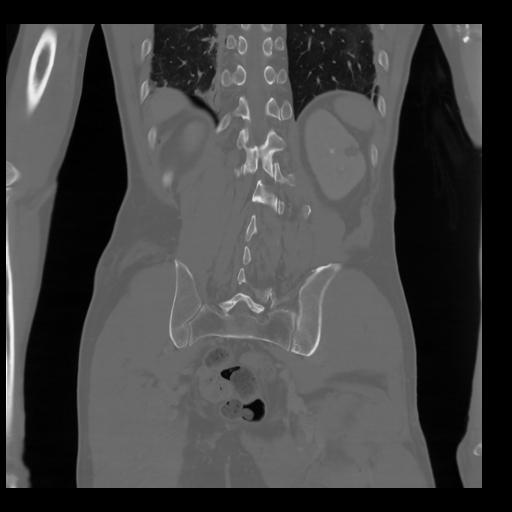

35 CUERPO,CE,Coronal,3.000,CUERPO,Coronal,